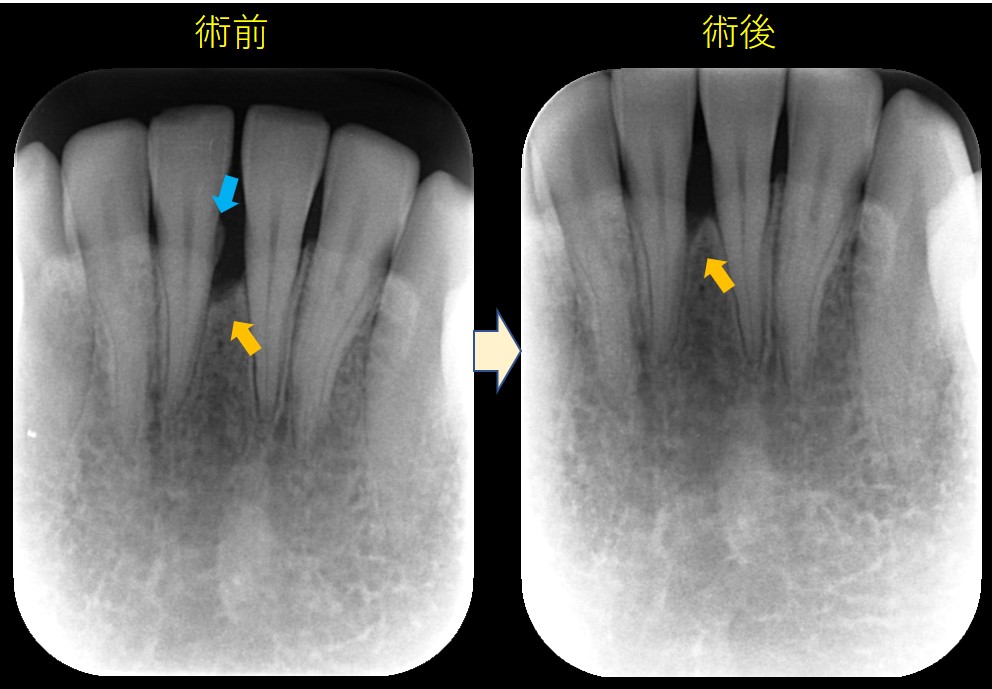

222.歯槽骨の再生 歯周基本治療

術前の写真では、青矢印部分に大きな骨吸収が確認できます。歯の動揺もありました。術後の写真では、青矢印部分に歯槽骨の再生が確認できます。

治療は?

歯の安静を図る目的で、咬み合わせの調整を行いました。(しかし、歯が動いているからといって、闇雲に削ってはいけません。)

炎症をコントロールするために、口腔清掃指導(当院では歯間ブラシ→フロス→歯ブラシの順番)およびスケーリング・ルートプレーニングを行いました。スケーリング・ルートプレーニングは、歯茎の中の歯石を取り除き、歯根の表面を滑沢化することで、細菌の毒素を取り除くことを目的とします。

これらの治療を「歯周基本治療(非外科療法)」といいます。それでも治らない場合は、「歯周外科治療」を行うのですが、「歯周基本治療(非外科療法)」のみで改善する場合も多いのです。

今回も「歯周基本治療(非外科療法)」のみで歯槽骨の再生および歯周ポケットが改善しました。